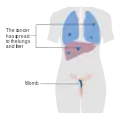

Stage 3 choriocarcinoma Stage 4 choriocarcinoma

Stage 4 choriocarcinoma